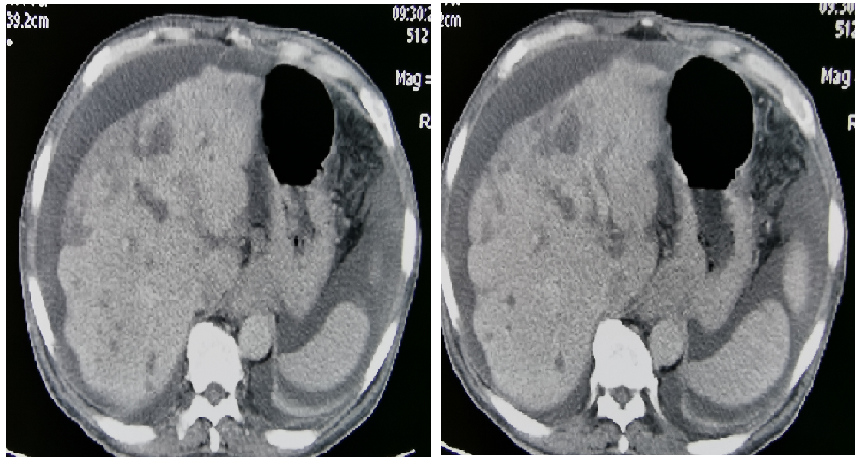

发病后CT(外院2017.11):贲门胃底部溃疡性肿物考虑恶性,腹腔多发肿大淋巴结,考虑转移。

图表1-1:发病后CT(外院2017.11)